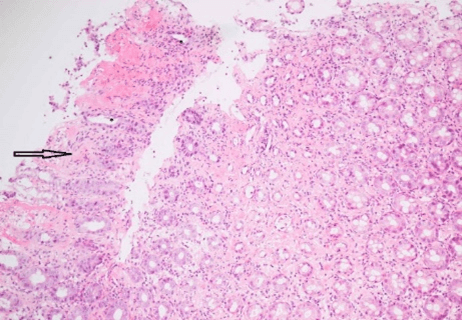

Figure 6: Descending colon (x10).

Asterisk: Atrophic crypts, Arrow: Hyalinised lamina propria.

Figure 8: Splenic flexure (x10).

The histology showed fragments of fibroinflammatory material along with some normal large intestinal mucosa. In other areas, the crypts were atrophic and withered in appearance with hyalinisation of the lamina propria and variable oedema. There was surface ulceration in the descending colon. Residual crypts contained acute inflammatory debris, and there was mild superficial active inflammation. The appearances were in keeping with ischaemic colitis. Critically, there was no evidence of dysplasia or invasive malignancy in the biopsy samples sent. He was managed conservatively with fluid hydration, nil per orally, and antibiotics in the hospital. He had a good resolution of his clinical condition before discharge.